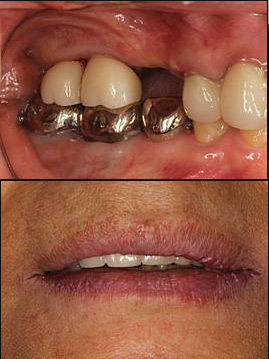

牙周治療結束後,Y小姐想整理牙齒外觀,透過圖一我們可以看到,製作多年後的假牙,因牙肉萎縮,有出現牙根外露的情形,Y小姐覺得不美觀,醫師也檢查出有咬合創傷的問題,雖然咬合創傷可以透過修磨牙齒,減少牙齒的損耗,但多次的修磨對牙齒也是一種傷害,若重新製作新的假牙可以幫助上下牙齒更少的接觸和損耗,還能夠延長牙齒生命,最後經過討論Y小姐決定重新製作新的假牙,製作前醫師會請技師來到現場為患者比色,並與患者一起確認顏色,透過圖二我們可以看到第一次假牙回來後試戴的樣子,結果出乎患者的意料,患者認為比想象中還要白,經過患者和醫師討論後決定重新再做一次假牙,從圖三可看到再次回來的假牙與前次的顏色有所不同,這次的結果患者是滿意的也能接受。

每個人的主觀意識都不同,能接受的樣子當然也會有所差異,對我們而言牙齒美觀我們會以患者的主觀感受為優先,那你會喜歡什麼樣的牙齒🦷呢?歡迎大家留言和我們分享~